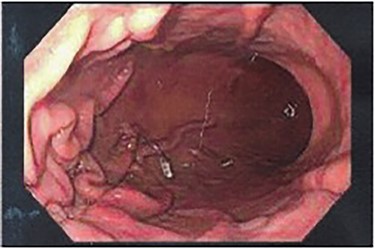

Patient subsequently underwent a robotically assisted laparoscopic paraesophageal hernia repair with mesh, partial gastrectomy with removal of gastric foreign bodies, and flexible endoscopy. Intraoperatively via initial laparoscopic approach, there was only noted to be small dimples along the greater gastric curve without any noticeable plication (Fig. 3). The stomach was twisted up into the hiatal hernia. Multiple permanent sutures with T-fasteners were seen on endoscopy, and attempts were made to remove these endoscopically without success. These sutures were not of full thickness, so a gastrotomy was made to remove them. Partial gastrectomy was performed, including the fundus. The diaphragm was repaired with interrupted silk sutures and reinforced with a bioabsorbable mesh. The patient recovered well and was discharged home on postoperative day two tolerating a diet. She was seen at follow-up with complete resolution of her preoperative symptoms.